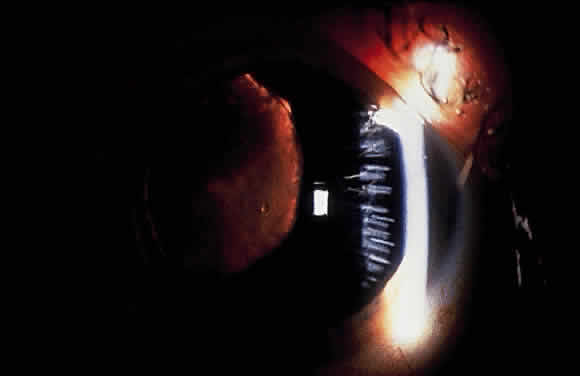

CLINICAL FEATURES

Pigment dispersion syndrome and pigmentary glaucoma are characterized by a generally vertical accumulation of pigment on the central corneal endothelium known as a Krukenberg spindle (Fig. 14). The usual pattern of pigment deposition results from a linear vertical junction of aqueous convection currents from the nasal and temporal halves of the anterior chamber.166 The pigment that accumulates on the corneal endothelium then undergoes phagocytosis by these cells. Although pleomorphism and polymegathism of corneal endothelial cells has been demonstrated on specular microscopic examination in eyes with PDS, the pigment does not appear toxic, since cell counts and corneal thicknesses remain normal in these eyes.180,181

Fig. 14. Vertical accumulation of pigment in central corneal endothelium (Krukenberg spindle) in pigmentary glaucoma.

Iris changes include deposition of pigment on the anterior iris surface and midperipheral iris transillumination defects of the iris pigment epithelium.166 If pigment deposition on the anterior iris surface is asymmetrical, heterochromia may be noted.166,182 In some asymmetrical cases, greater pigment dispersion has been noted in eyes with angle recession183 and in the cataractous eye in patients with unilateral lens opacities.184 The transillumination defects, which vary in severity from a few spokelike changes to 360° of involvement, can be seen by retroillumination achieved by directing a light through the pupil or by scleral transillumination166,185,186 (Fig. 15). A technique known as infrared transillumination videography allows visualization and documentation of iris defects that may not be visible on slit-lamp examination.187

Fig. 15. Spokelike midperipheral iris transillumination defects in pigmentary glaucoma as seen by retroillumination.